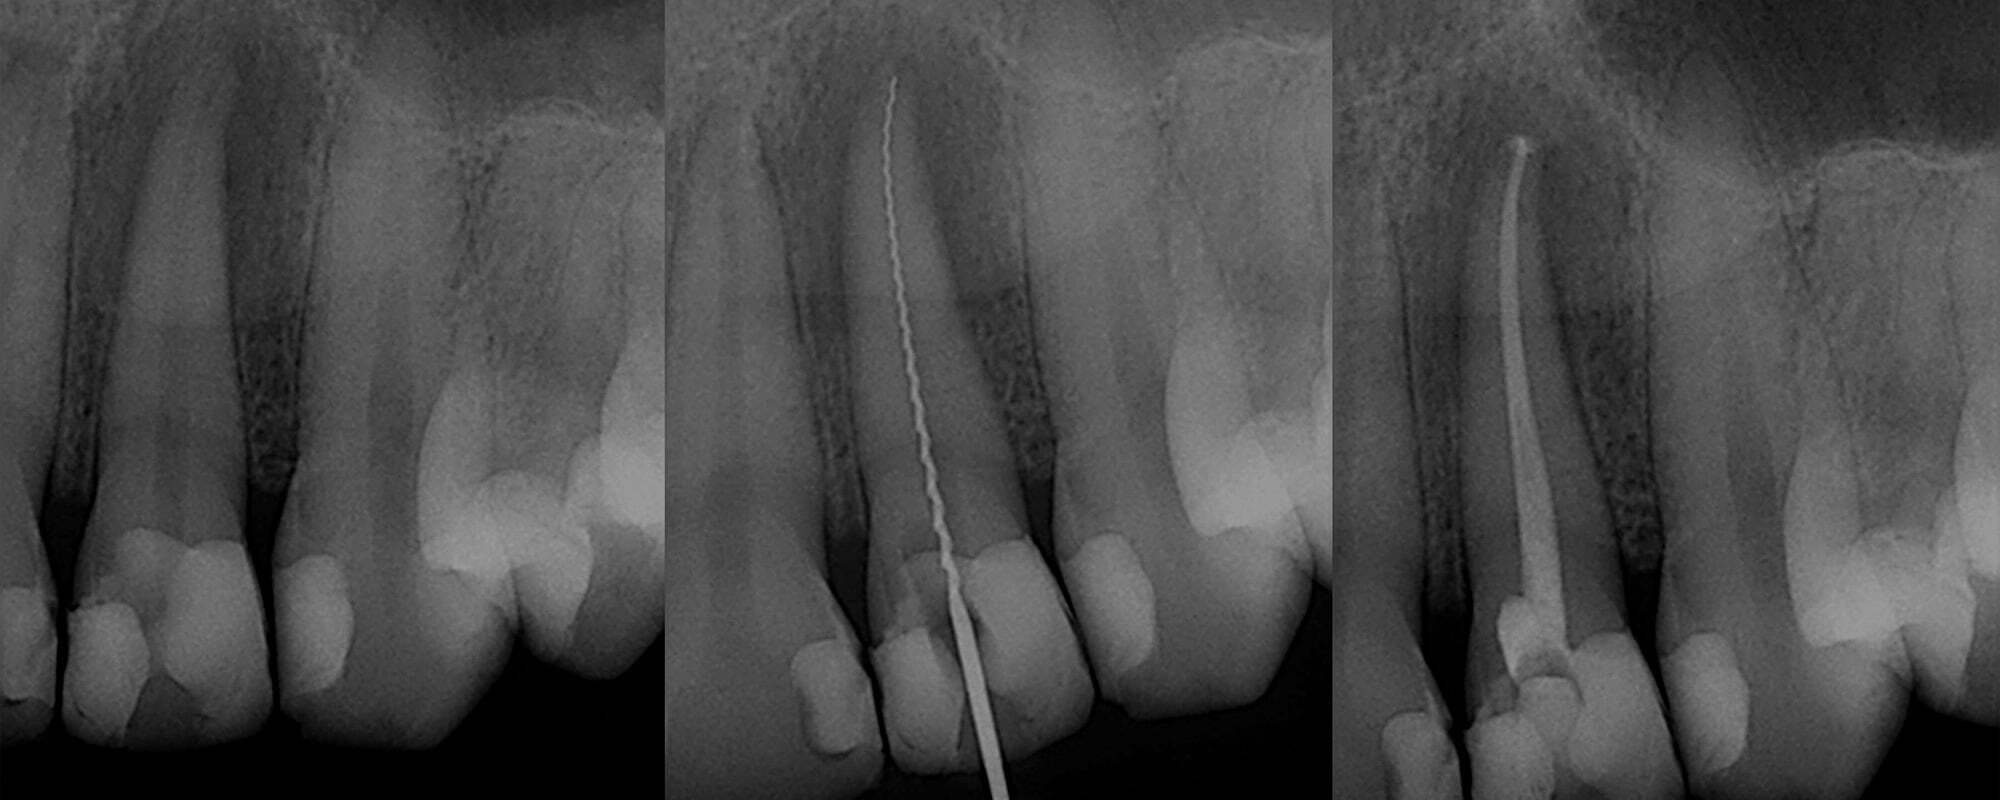

Root canal dental surgery Stock Image C029/0466 Science Photo Library